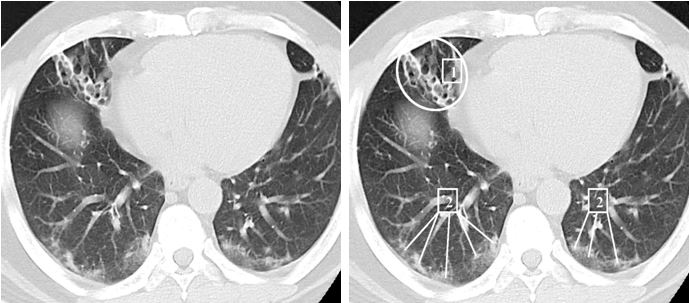

КТ ретроперитонеального фиброза: Изображения и диагностика